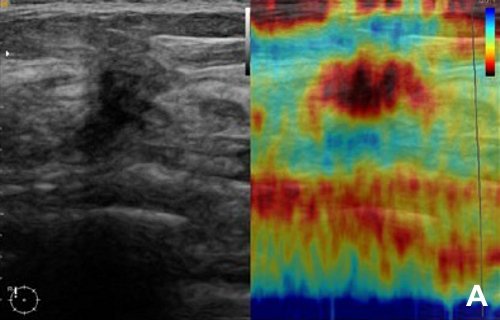

Эластография молочной железы: слева B-режим, справа эластограмма.